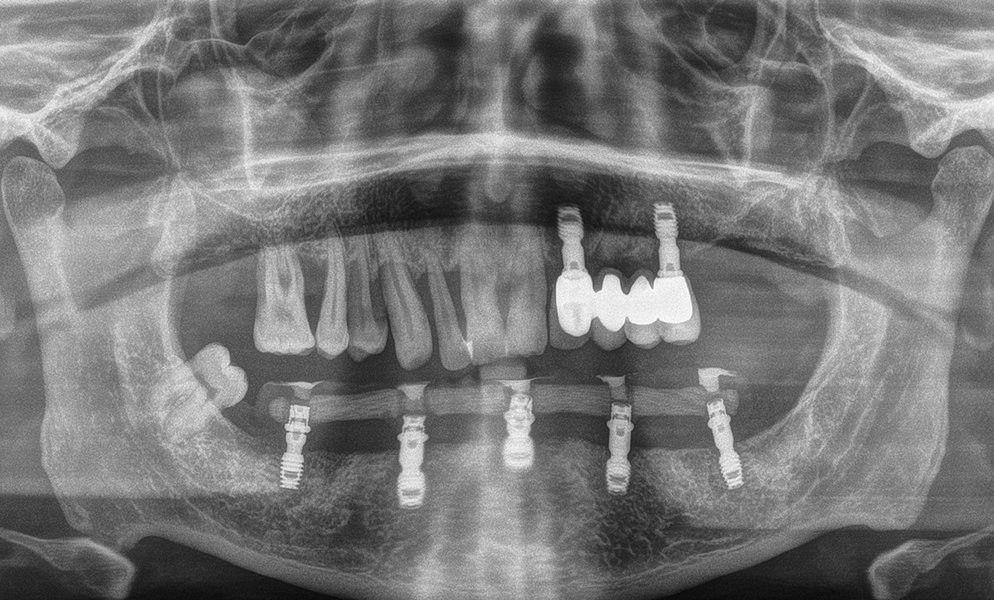

| Before | After |

![]() |

| Lower teeth extraction and immediate short dental implant (Bicon, USA)- placement | |